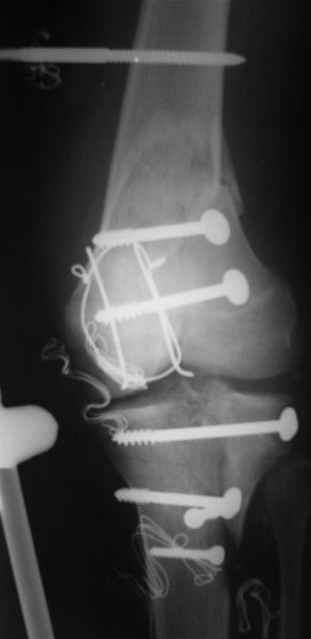

Отправитель: Evgueny Tschekashkin 14 Декабрь 2004, 18:41

Вид раны на сегодня...

4 cутки после травмы.

Спасибо за комментарии. Травма тяжелая с проблематичным прогнозом для функции коленного сустава( изначально травма разгибательного аппарата с последующим частичным некрозом собственной связки надколенника и о обнажением рефиксированного фрагмента бугристости большеберцовой кости, дефектом центрального отдела суставной поверхности большеберцовой кости и медиального отдела капсулы сустава).